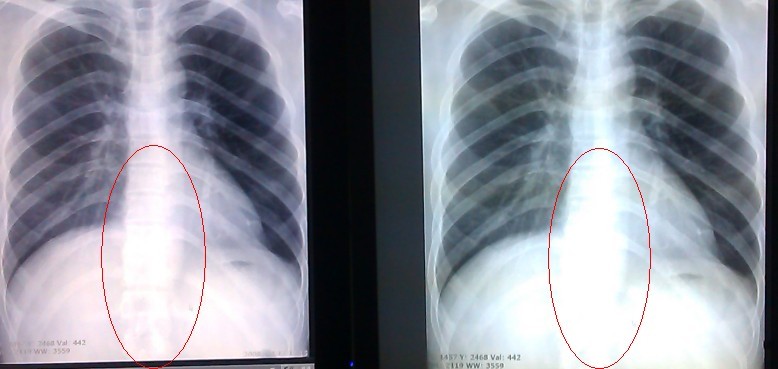

大家好!现给两个对比图给大家看下,2M灰阶显示器,左边是迈特菲,右边是日本知名品牌,比较明显,清晰度比较好,所有的设置参数都一样,但是显示效果确不一样!

显示器对比.jpg

1.jpg